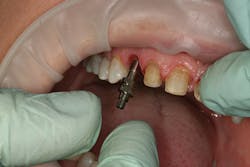

After approval of the diagnostic wax-up, profound anesthesia in the area of Nos. 6 through 11 was achieved (Septocaine, Septodont). Following sounding for bone to confirm adequate biologic width, laser soft-tissue recontouring in the areas of Nos. 6 through 11 was performed using an Er;Cr:YSGG soft- and hard-tissue laser (Waterlase, Biolase). Teeth Nos. 7, 8, 9, and 10 were prepared for conventional porcelain laminate veneers. Implant crowns were sectioned and removed from Nos. 6 and 11 (figure 4). To verify the radiographic implant identification, the abutments were removed and impression copings were tried in and radiographic seat was confirmed. The abutments were then replaced to serve as provisional restorative components. Screw access holes were blocked out and the provisional stent was used to fabricate provisional restorations on Nos. 6 through 11 (Luxatemp Ultra BL, DMG America) (figures 5, 6).

Figure 4